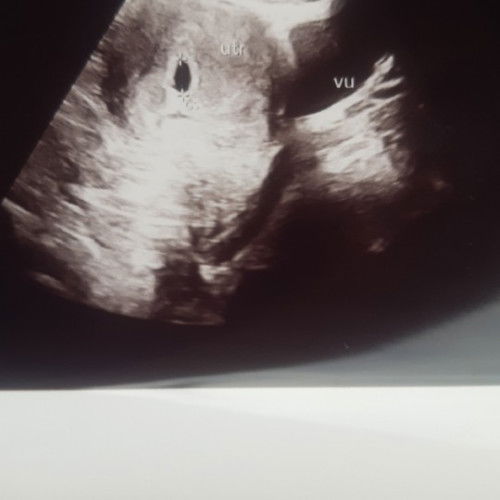

Usia kandungan 5w6d

Tadi siang USG dan hasilnya masih terlihat kantongnya .disuruh USG lagi 1 bulannan lagi. Ada yang sama kah? . Semoga USG berikutnya sudah terlihat bakal janin dan djj sehat2 y bun